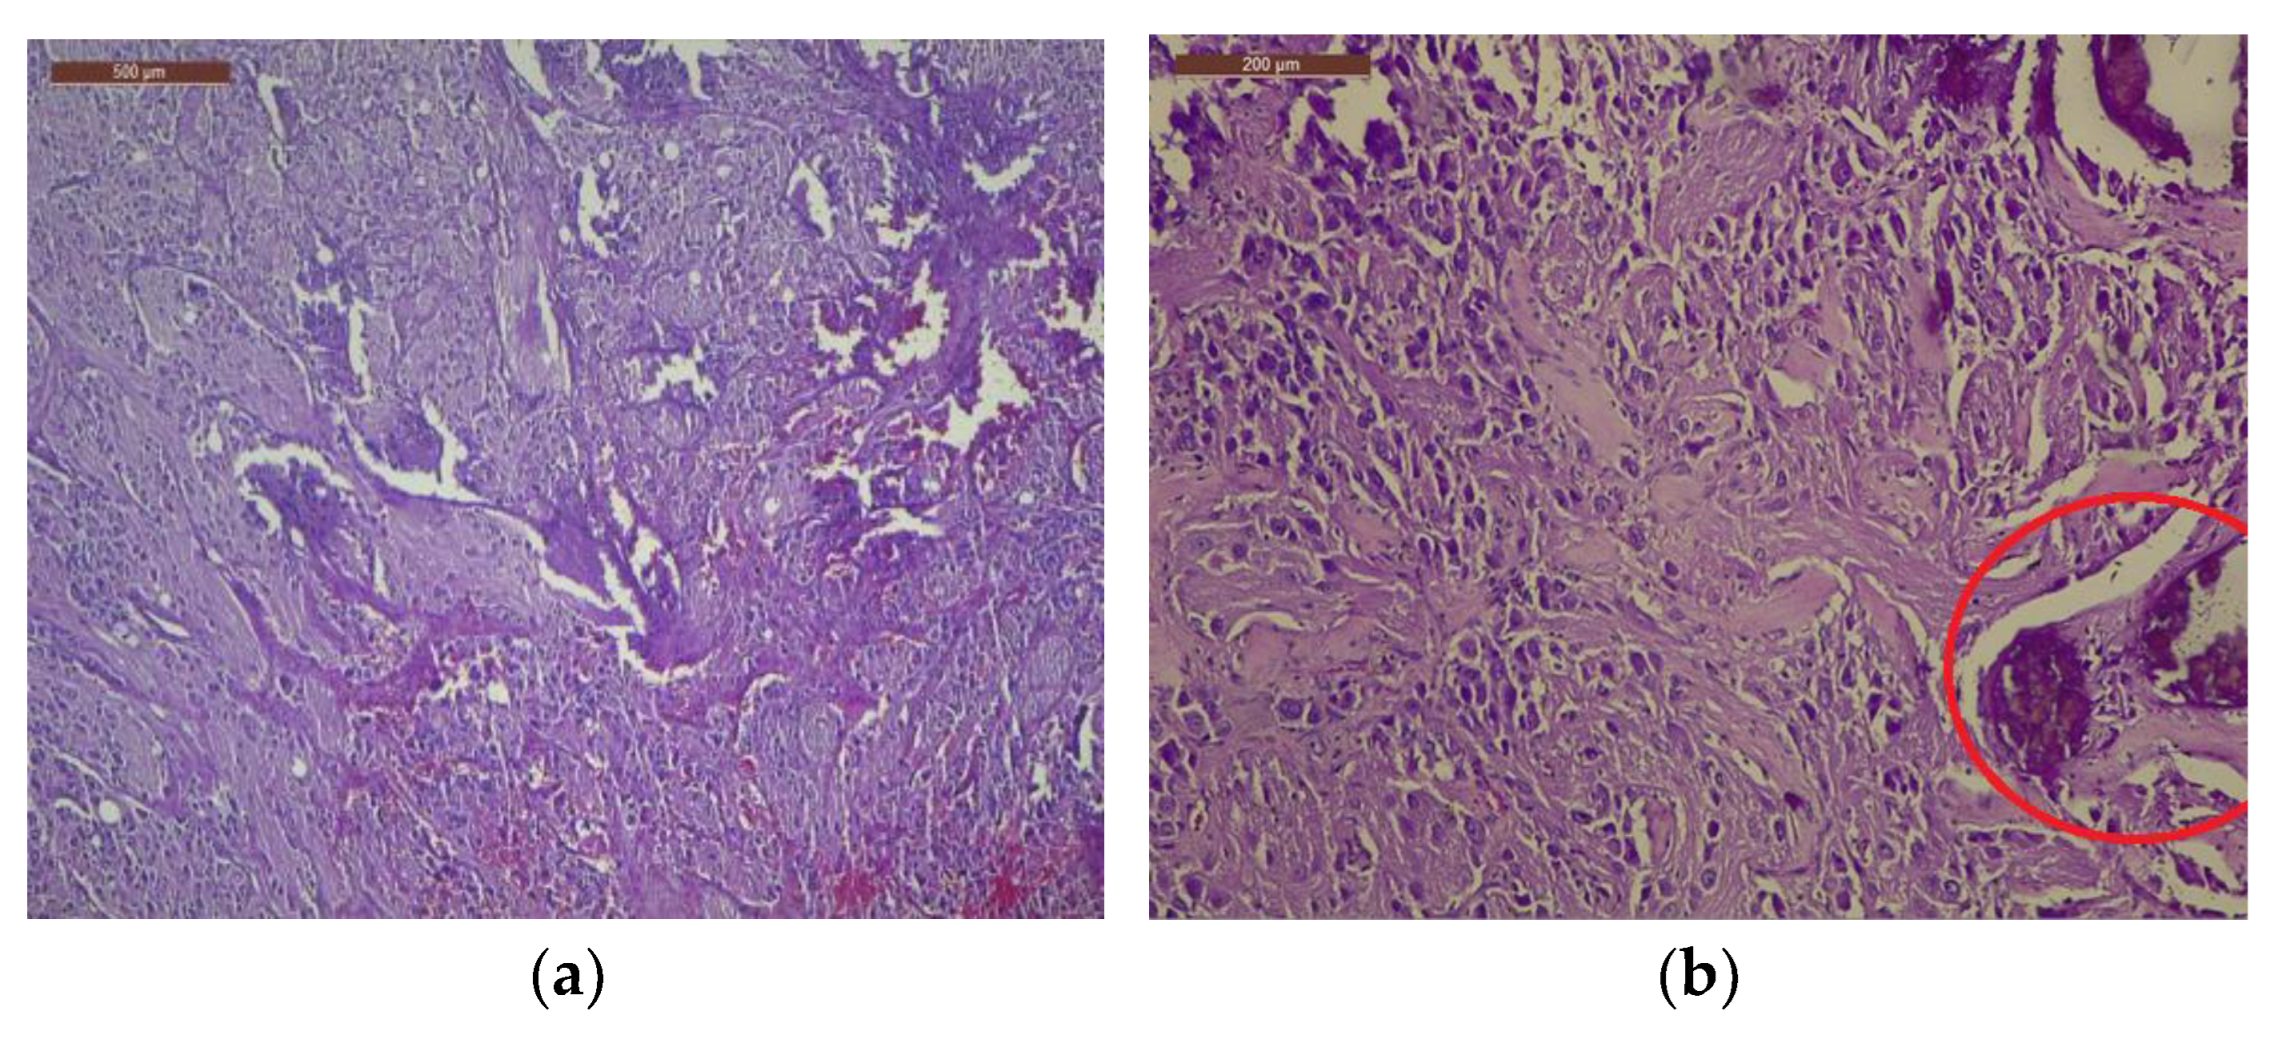

The tumor was histologically determined to be an INSS II-localized ganglioneuroblastoma intermixed with a stroma-rich (Shimada Classification) tumor with complete gross excision, positive lymph nodes, and a low MKI (mitosis-karyorrhexis index) of less than 100. The growth pattern of the tumor was solid/lobular. Large, round-to-ovoid nuclei and an abundance of basophilic cytoplasm were features of the tumor cells. A “salt and pepper appearance” with prominent nucleoli and alternate regions of euchromatin and heterochromatin was seen. Other tumor cells were distinguished by rich, eosinophilic cytoplasm, eccentric nuclei, and prominent cell boundaries. The tumor cells contained a small quantity of bleeding and had somewhat calcified dystrophic regions (Figure 4).

Figure 4. Visualization of tumor cell nuclei characterized by conspicuous enlargement, accompanied by discernible nucleoli and cytoplasm exhibiting a dense eosinophilic nature: (a) Within the tumor cell population, minor regions of hemorrhage have been noted, 4× magnification; (b) observe the tumor’s growth pattern displaying either lobular or solid arrangements, accompanied by notable instances of dystrophic calcification, 10× magnification. The examination was performed using H&E staining. H score for NSE = 235, NF200 = 230, S100 = 298, GFAP = 288.